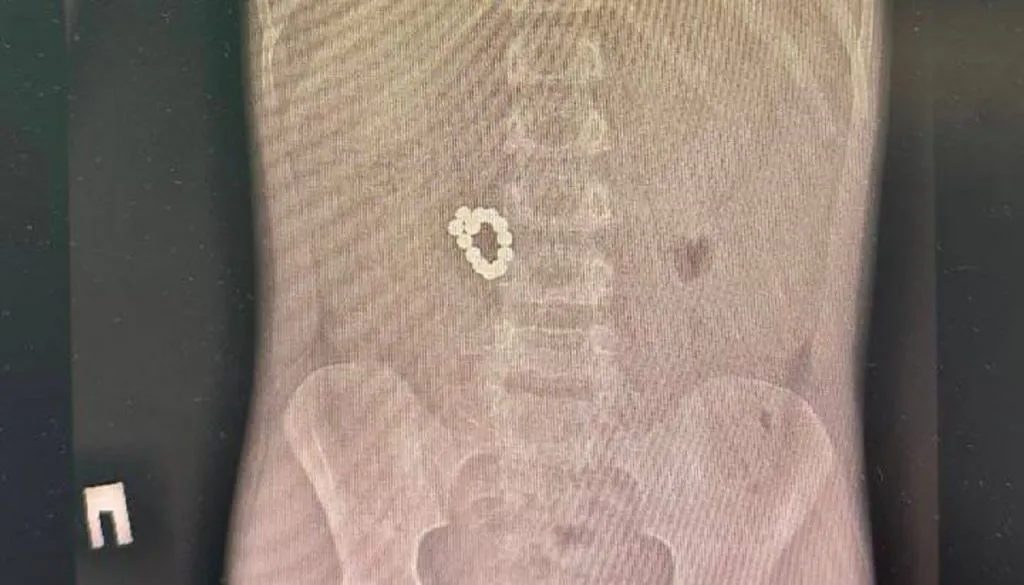

«При проведении рентгенографии органов брюшной полости был выявлен конгломерат из множества металлических предметов размером 6,2 × 2,2 см. Ребёнка экстренно госпитализировали для удаления инородного тела», - сообщили в управлении здравоохранения города.

Сначала врачи попытались извлечь предметы эндоскопическим путём. Но магниты собрались в такой плотный комок, что сделать это было невозможно. Решили оперировать и извлекли из желудка ребёнка 105 магнитных бусин!